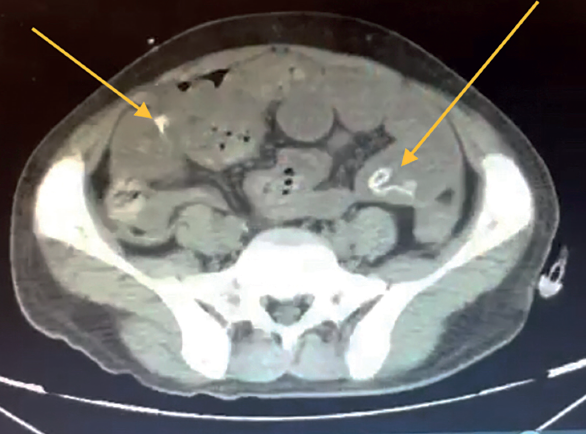

Se le realizó tomografía axial computada el 10-05-2021, donde se identificó: asas de intestino delgado de contenido heterogéneo a expensas de gas y líquido, múltiples imágenes amorfas hiperdensas con atenuaciones que van de 252 HU a 820 HU, en duodeno y yeyuno, así como estriación de su grasa, hacia íleon presenta dimensiones y morfología conservados. Colon con material de residuo en su interior, así como material hiperdenso y disminución de su calibre desde su porción descendente. A nivel de grasa mesentérica adyacente a región ileocólica se observa estriación así como congestión de vasos a ese nivel e imágenes saculares dependientes de pared. Escaso aire libre perihepático, perivesicular y subdiafragmático. Conclusión ileítis con datos de íleo. Neumoperitoneo duodeno y yeyuno de contenido heterogéneo de etiología a determinar. Estriación de la grasa y congestión de vasos mesentéricos (figuras 2 y 3).

Figura 3 Colon con material de residuo en su interior, así como múltiples materiales hiperdensos y disminución de su calibre desde su porción descendente. A nivel de grasa mesentérica adyacente a región ileocólica, se observa estriación, así como congestión de vasos.